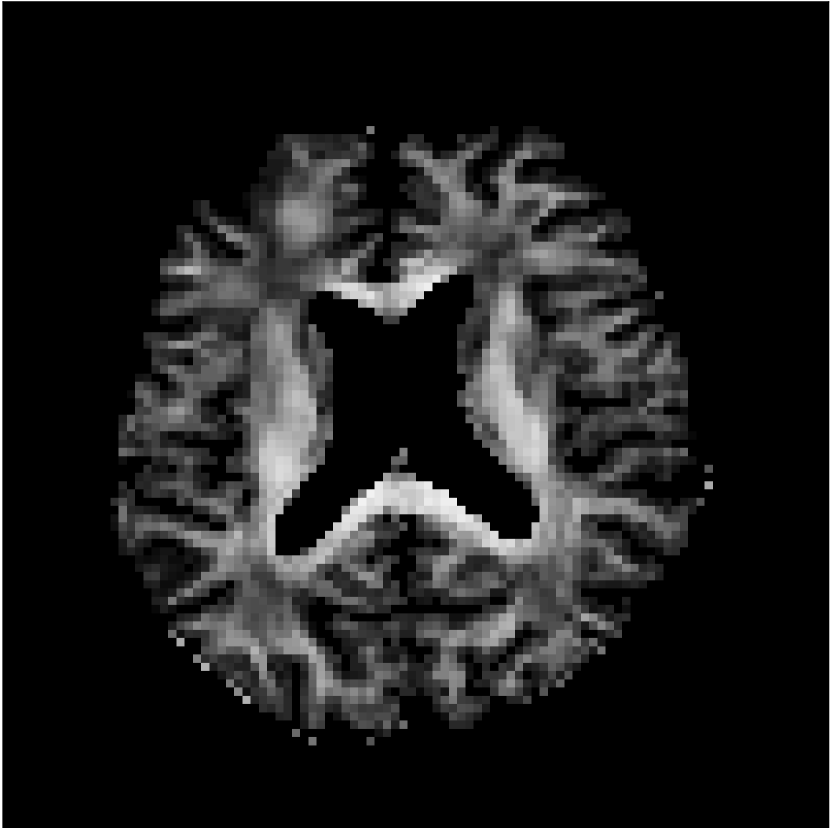

Figure 10 compares mean diffusivity maps across various partial Fourier factors between the CCNN and state-of-the-art methods.

No PF

7/8 PF

6/8 PF

5/8 PF

SoA

MD, μ𝜇\mum2/ms

CCNN

Figure 10: Comparison of mean diffusivity (MD) parameter maps across PF factors of 5/8ths, 6/8ths, 7/8ths, and without PF (No PF). The methods include state-of-the-art (SoA) and CCNN methods. Without partial Fourier, both methods are similar; however, as the PF factor increases, substantial artifacts are introduced in the SoA method, particularly around the lateral ventricles. The CCNN method is able to reduce the introduction of artifacts.

The methods perform similarly without partial Fourier acceleration, but as partial Fourier acceleration increases, the image is continually degraded in the SoA method, with "black voxels" appearing around the lateral ventricles. The CCNN method mitigates the appearance of these artifacts in the parameter maps.